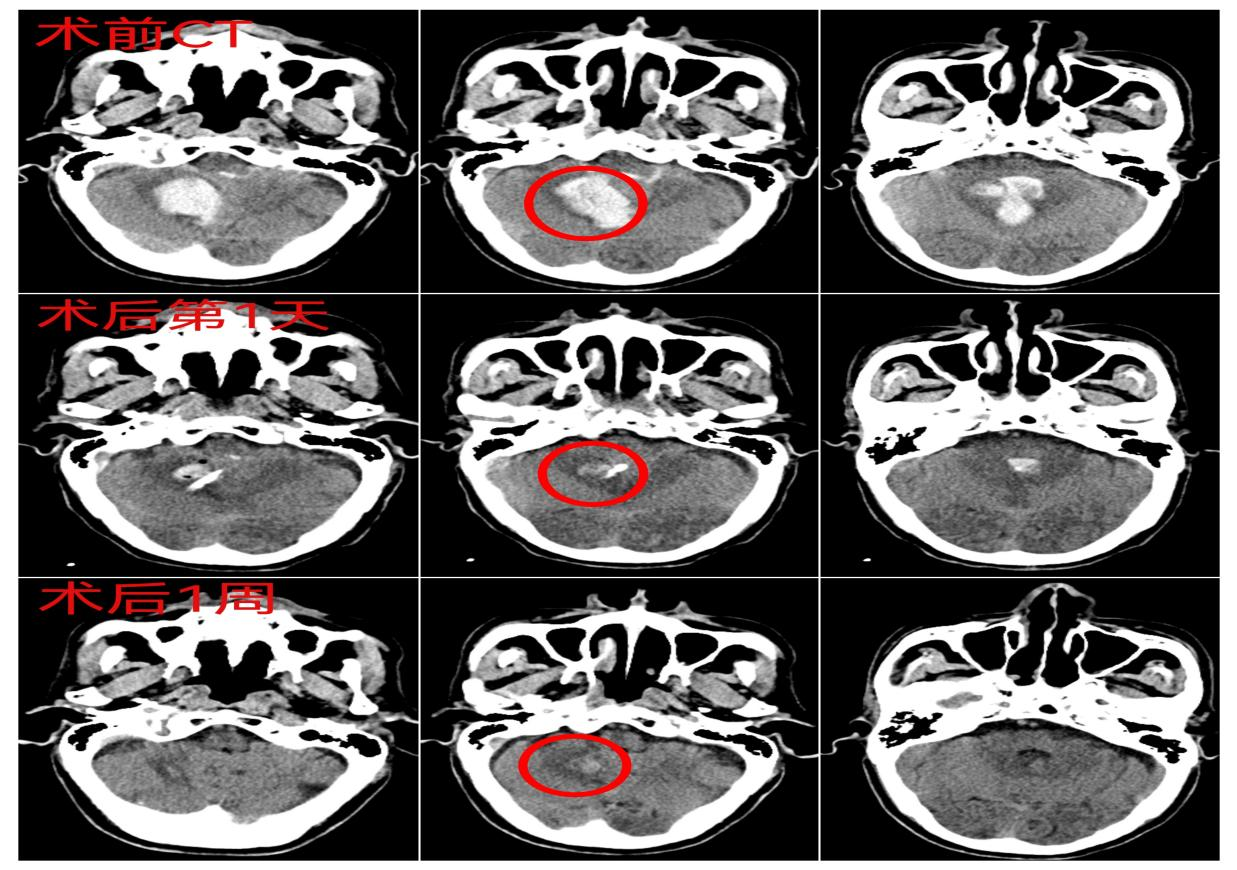

“该患者右侧小脑出血并破入脑室系统,出血量约12ml左右,头颈联合CTA已排除颅内动脉瘤破裂。”伴随着影像科主任康龙山明确的影像诊断,神经外科副主任王勇带领科室团队迅速将患者王爷爷送至病房。

术后第一天复查头颅CT,提示王爷爷颅内血肿基本清除,未见明显迟发性颅内出血。

术后一周复查头颅CT,提示颅内血肿已吸收,王爷爷在家人的辅助下,下床进行康复训练。